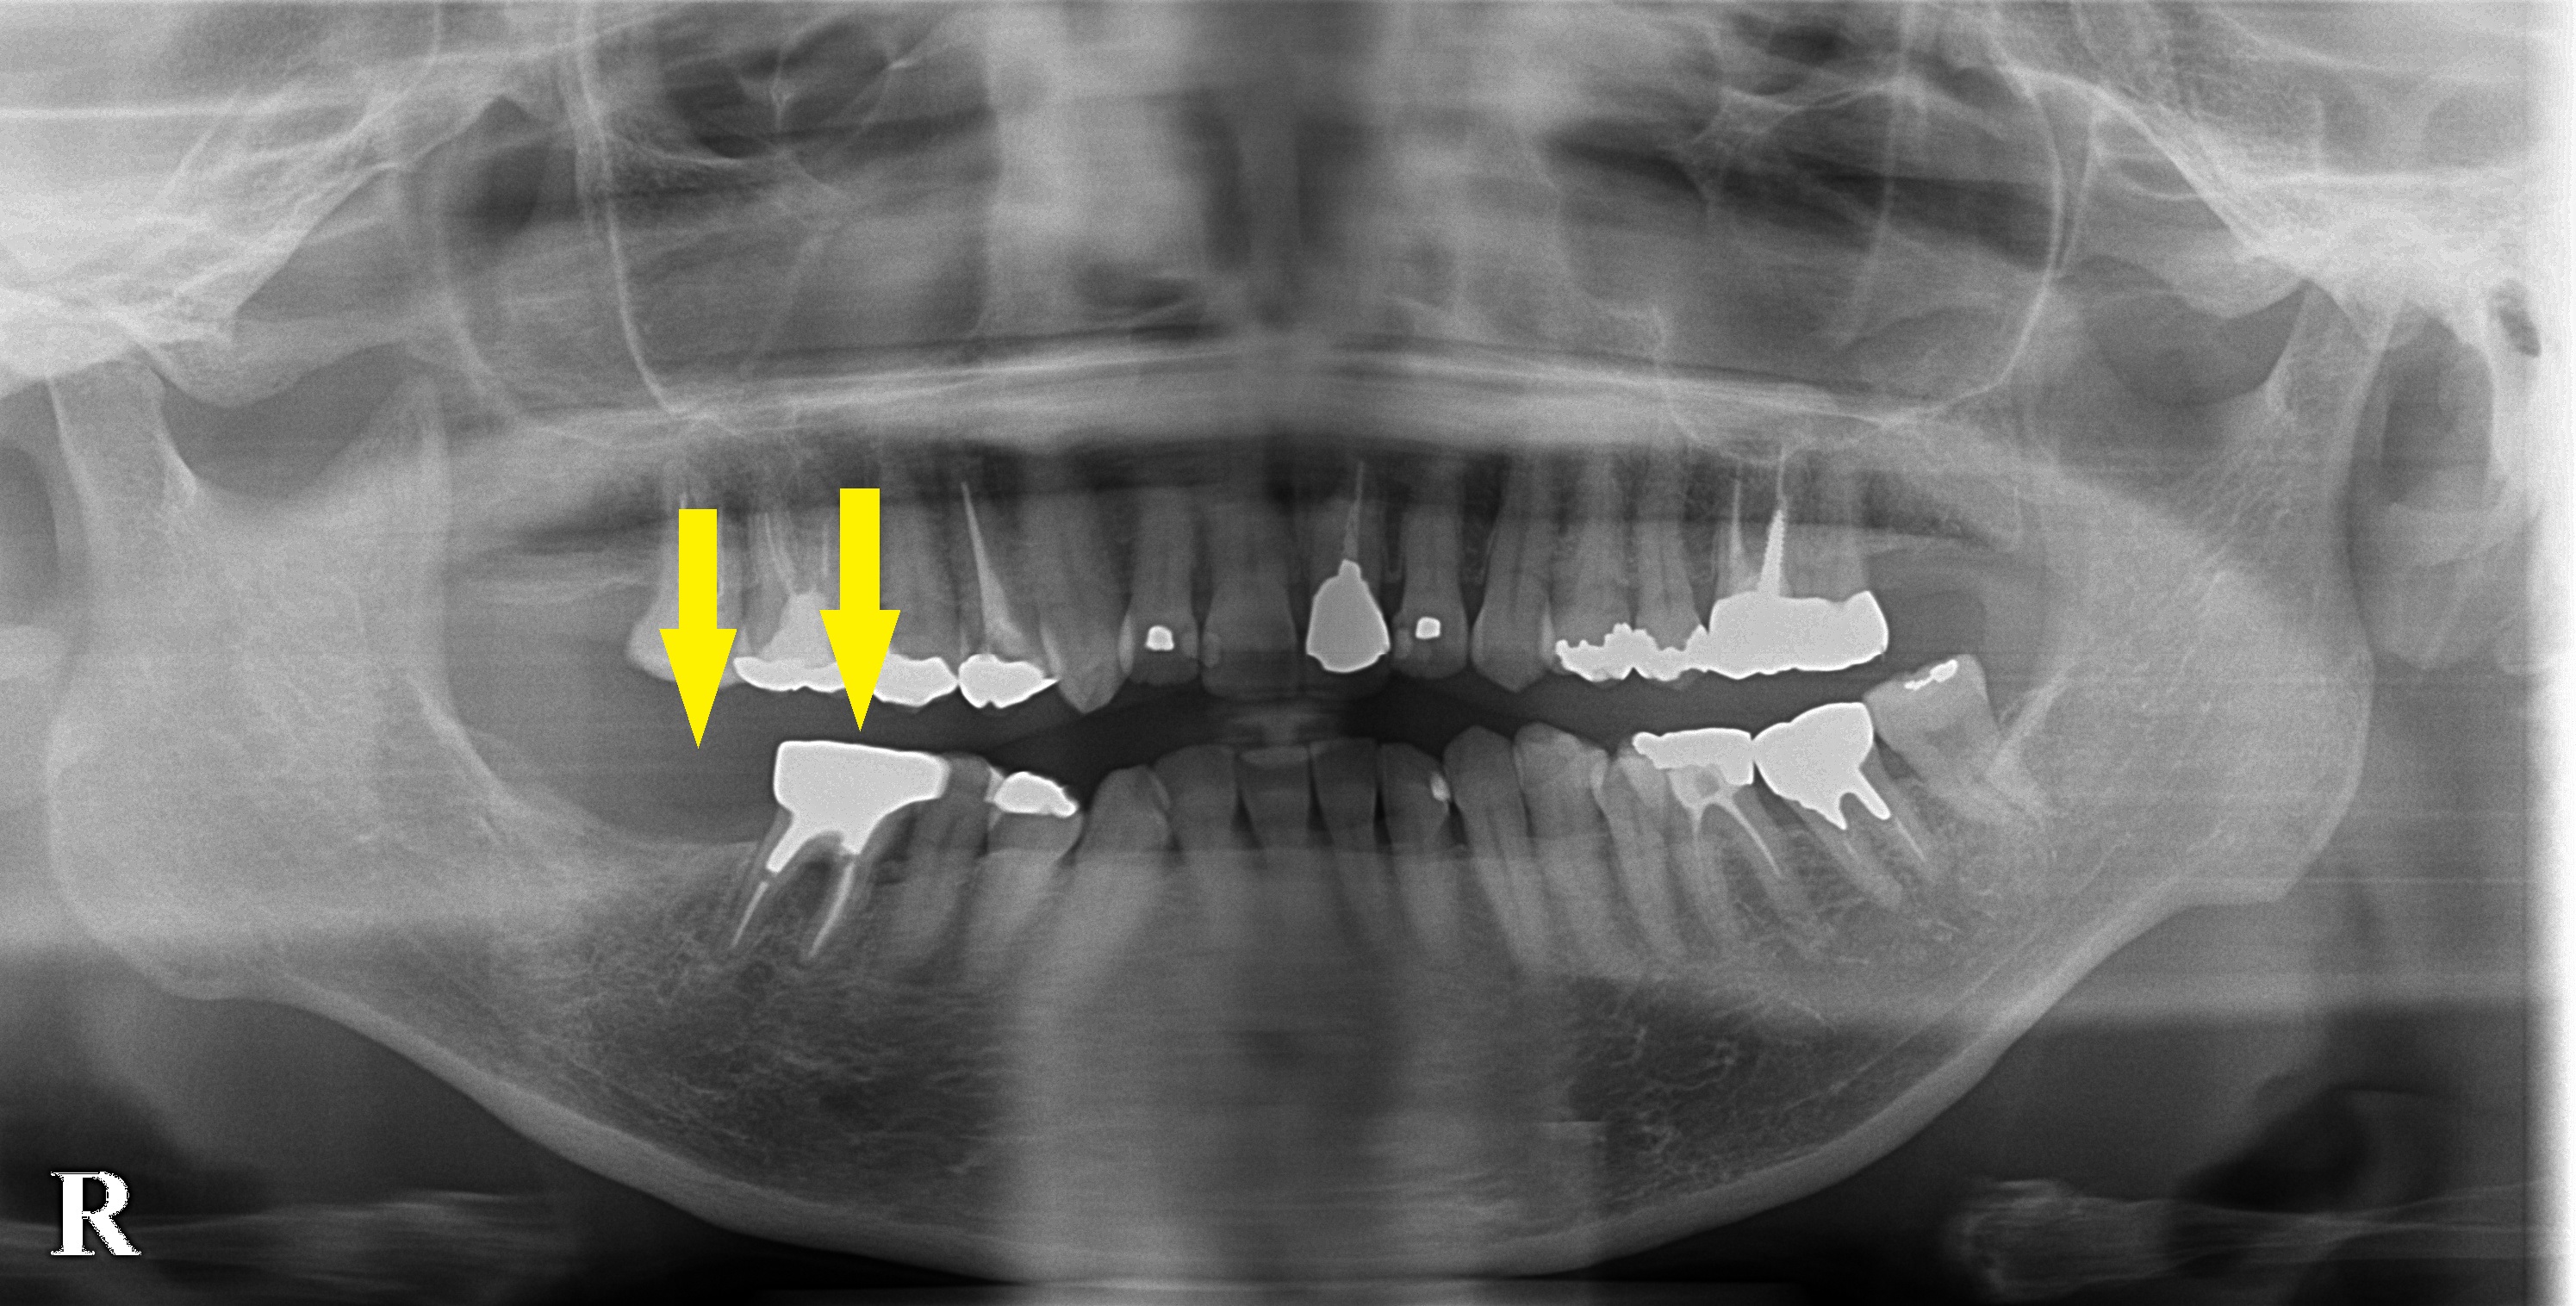

レントゲン写真だけ見ると、それほど悪いようには見えないのですが、CTを撮ってみると、歯根の先の方まで、歯槽骨が吸収され、おそらく、歯根部分に亀裂があるか、穴が開いていて、炎症が重度の状態になっていると考えられました。